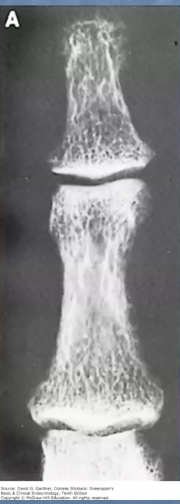

Quelles sont les signes d’hyperparathyroïdie primaire à l’imagerie?

A

Radiographie des os longs : Osteitis fibrosa cystica

• Résorption sous-périostée

• Tumeurs brunes

• Kystes osseux

• Apparence poivre et sel à la radiographie du crâne

Ostéodensitométrie : ostéoporose